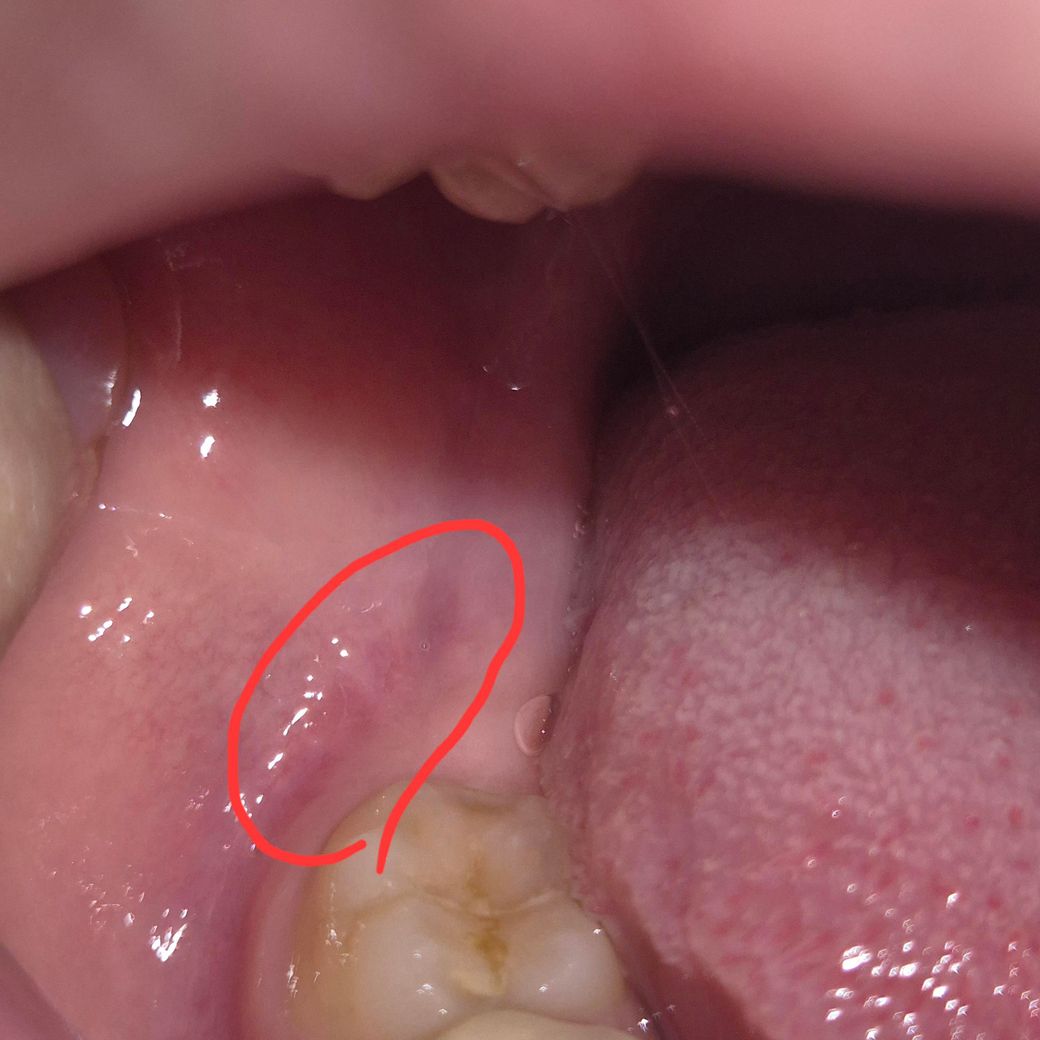

맨 끝쪽 잇몸에 염증 방치하면 어떻게 되나요

제가 부정교합이 있는 건지 오른쪽으로만 씹게 되면, 왼쪽 끝(사랑니 나는 부분) 잇몸에 윗니가 자꾸 닿습니다.

근데 지금 오른쪽으로만 식사를 해야 되는 상황이라 몇 달 째 이러고 있으니, 끝잇몸이 욱신거리고, 빨개지고, 치아 자국도 나고, 붓고 그럽니다.

사진 상 빨간 동그라미 친 부분이 아픕니다.

(참고로 왼쪽 위, 아래 사랑니는 뽑아서 없는 상태입니다.)